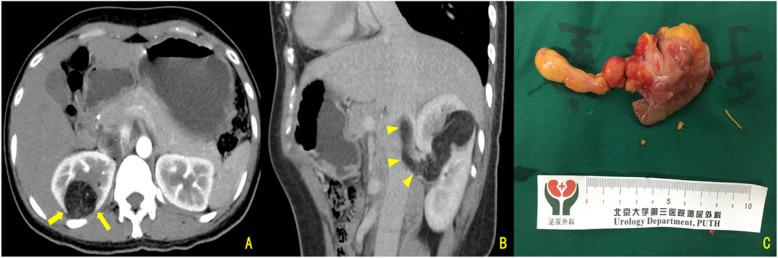

Results: Enhanced CT showed renal sinus involvement in all CAML cases versus four ccRCC cases (p = 0.002). All primary CAML tumors had fatty components, compared to one ccRCC case (p < 0.001). Enhanced CT also revealed 7 VTTs with fatty components (6 in the CAML group) (p < 0.001). Thrombus lengths in the inferior vena cava (IVC) were 8.05 ± 2.22 cm for CAML and 5.29 ± 2.38 cm for ccRCC, with no significant difference (p = 0.610). The maximum/minimum anteroposterior VTT diameter ratios were 3.98 and 1.09, respectively (p < 0.001); coronal diameter ratios were 4.00 and 1.12, respectively (p < 0.001). Ultrasound revealed that, except for one Mayo Level 0 case, the involved IVC in the CAML group had continuous, intact walls with blood flow signals in the residual lumen, while in the ccRCC group, most VTTs had unclear boundaries and only one case showed blood flow signals in the residual lumen (p = 0.001). Intraoperative blood loss was significantly lower in CAML cases (p = 0.017). No CAML patient had VTT invading the venous wall, unlike 8 ccRCC patients (p = 0.016). All patients were followed for 21-74 months (median: 34.5 months, mean: 36.6 months). All were alive with normal renal function, and no tumor recurrence or metastasis was observed.

Conclusion: Renal CAML with VTT is characterized by three imaging features: the presence of fatty components, a unique geometric growth pattern, and the absence of venous wall invasion, potentially serving as valuable indicators for differentiating CAML from ccRCC lesions.